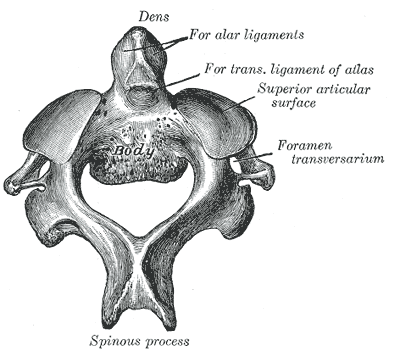

Https www alamy de die katze eine einfuhrung in das studium der backboned tiere vor allem saugetiere katzen anatomie vergleichende 42 die katze chap iiiahneln die funfte zervikalen die siebte jedoch hat eine langere dornfortsatze prozess wie von einem brustwirbel und nur keine wirbelsaule ganal dass ein teil der transversalen prozess entwickelt werden die mit root uber dem wirbelkanal und mit der ein apophysis prozess der transversalen prozess des funften wirbel entspricht diese teile daher konnen getroffen werden zu vertreten abb 20 die achse wirbel a in der seitenansicht b in der vorderansicht c zuruck image235092628 html (Dateityp jpg)

Die Katze Eine Einfuhrung In Das Studium Der Backboned Tiere Vor Allem Saugetiere Katzen Anatomie Vergleichende 42 Die Katze Chap Iii Ahneln Die Funfte Zervikalen Die Siebte Jedoch Hat Eine Langere Dornfortsatze